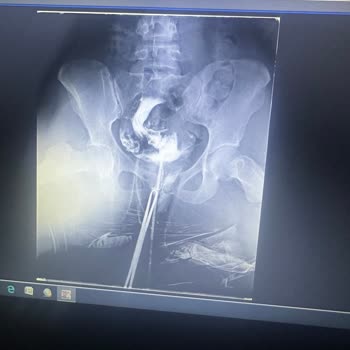

11 Mart’ta başarısız olan ilk girişimin ardından bu kez ilaç verildi ve 12 Mart 2026’da yeniden anestezi altında ikinci hsg çekimi yapıldı. Böylece iki gün üst üste, iki kere anestezi almak zorunda kaldım. Kollarımda morluklar oluştu, kasıklarımda çok şiddetli ağrılar yaşadım ve tedavi sürecim yaklaşık iki ay geriye atıldı. Üstelik ikinci işlem sonrası verilen CD’deki görüntüler de net ve değerlendirilebilir değildir.

Bu işlemler için toplam 16.300 TL ödedim. Yaşadığım sorunları hastane müdürü**** ilettiğimde bana işlemi ücretsiz olarak tekrar çekmeyi teklif etti, ancak ben üst üste iki defa aynı sorunu yaşamışken üçüncü kez aynı hataya düşmek istemediğimi açıkça belirttim. Sonuç olarak, iki kez çekilen hsg filminden hiçbir tıbbi sonuç elde edilemedi, bu nedenle işlemi başka bir yerde tekrar yaptırmak zorunda kalacağım.